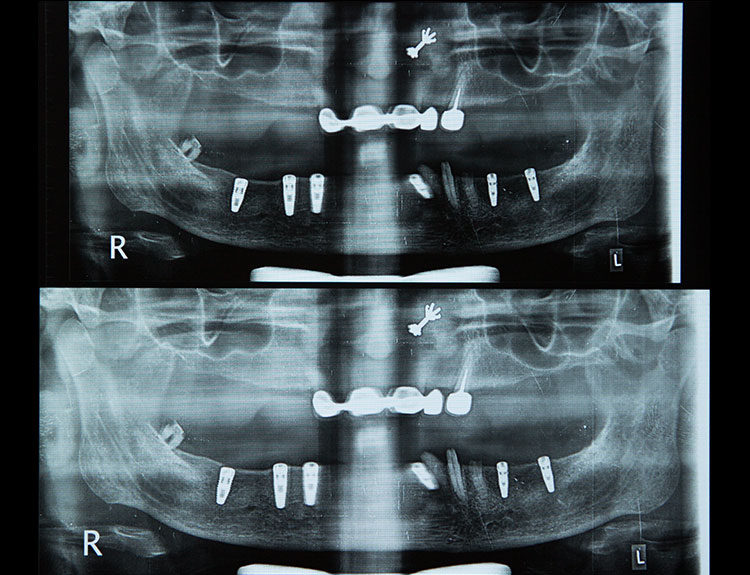

Dental implants are artificial tooth roots made of medical-grade titanium that are surgically placed into the jawbone. Once the implant integrates with the bone, a crown is fixed on top, giving you a strong, natural-looking replacement tooth.

If you are searching for reliable Dental Implants in Punjabi Bagh, Dental Que provides personalized solutions based on your oral health, bone condition, and smile goals.